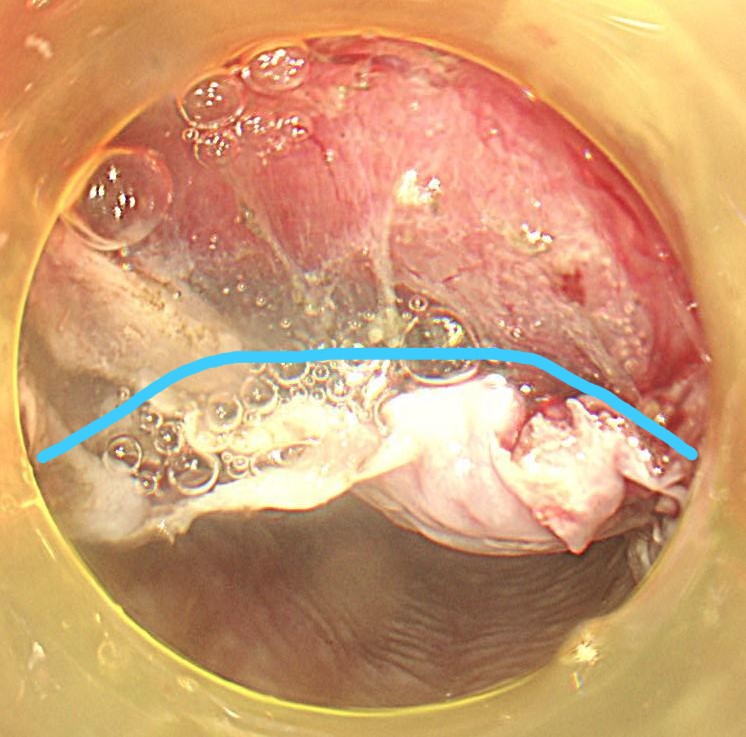

マーキング後にその外周に粘膜切開を行います。粘膜下局注はムコアップを使用し、デュアルナイフ1.5mmを用いてエンドカットモードで切開していきます。

粘膜下層剥離術を開始します。粘膜下局注はムコアップを使用しています。デュアルナイフ1.5mmでスイフトコアグ30で少しずつ剥離していきます。